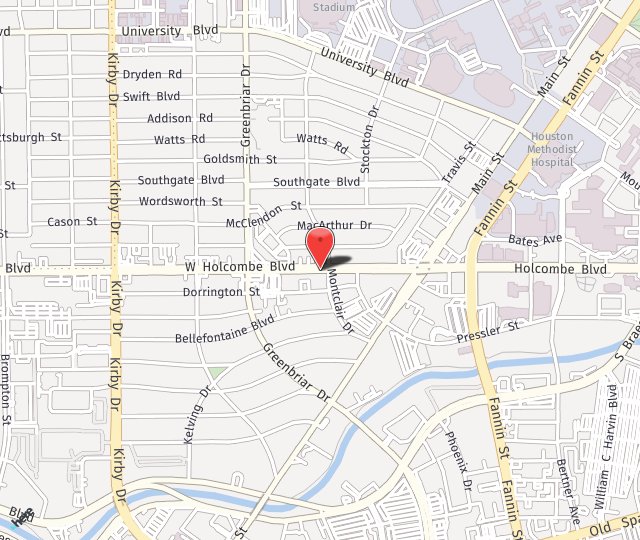

View Angle: front

Before